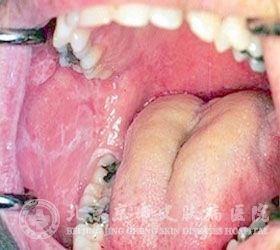

现在,有很多人患有口腔扁平苔藓,给人们的生活工作带来了严重的影响。并且口腔扁平苔藓比较顽固,让人们非常烦恼,不仅给人们的身体造成了一定的影响,而且还伴有各种不良症状,为了避免加重自己的疾病,同时加强对皮肤病知识的了解,北京京城皮肤医院就给大家讲解,如何鉴别和诊断口腔扁平苔藓。

如何鉴别和诊断口腔扁平苔藓

北京京城皮肤医院指出,口腔扁平苔藓是一种比较常见的口腔非感染性黏膜疾病,是一种慢性的皮肤、粘膜性疾病。它的出现给患者带来了很大的伤害,因此得了口腔扁平苔藓,一定要及时的治疗,只有正确的鉴别和诊断口腔扁平苔藓,才能减少出现误诊误治状况的发生。下面我们一起了解一下如何鉴别和诊断口腔扁平苔藓。

口腔扁平苔藓的早期为烛光白色的条纹,为多角形的红色丘疹且周围因充血而发红,有时会变现为溃疡或糜烂,一般病程较长,而且很高,一般好发于四肢、眼部和生殖器部位,一般是由于肾虚上火所致。